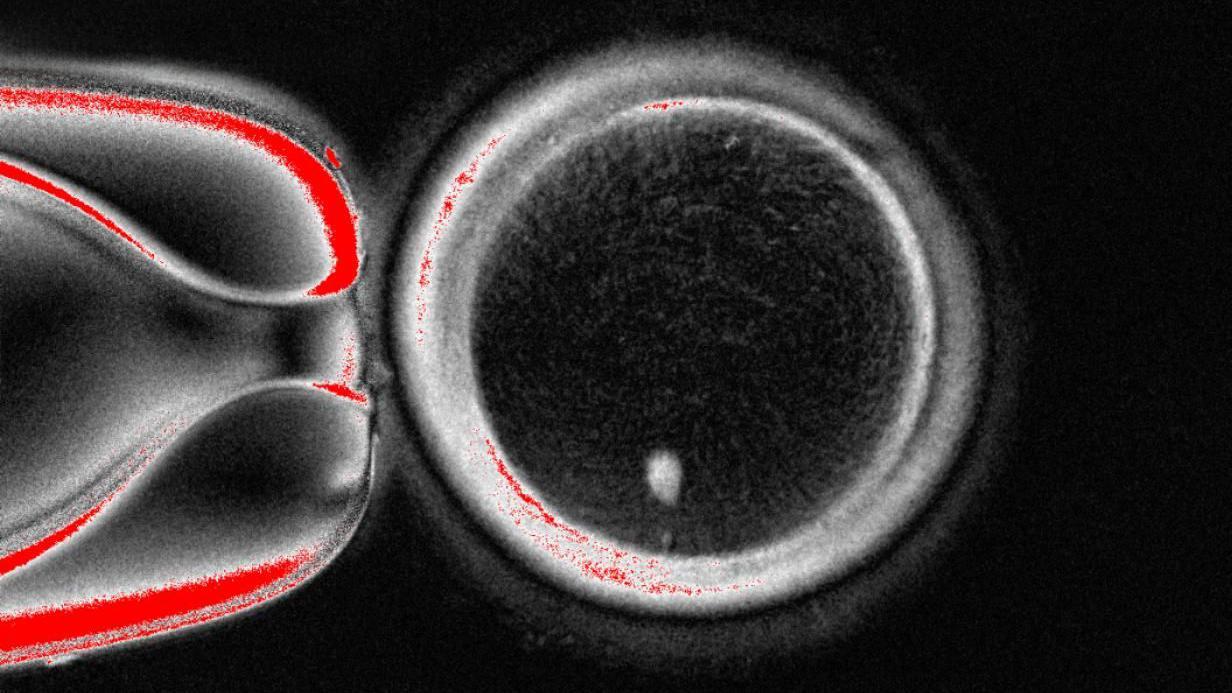

Studija, objavljena u naučnom časopisu Nejčer komjunikejšns, prikazala je da su napravljene 82 funkcionalne jajne ćelije.

Bile su oplođene spermom, a neke su stigle čak do ranih stadijuma razvoja embriona.

Nijedan nije razvijen posle šestodnevnog stadijuma.